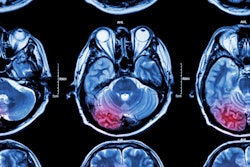

German researchers are recommending the use of diffusion-weighted MRI (DWI-MR) instead of CT to diagnose acute ischemic stroke within 12 hours of a person's first stroke symptom, according to new guidelines published in the July 13 issue of Neurology.

The study found that DWI-MR images identified stroke 83% of the time, compared with 26% for CT. DWI also more accurately detected lesions from stroke and helped identify the severity of some types of stroke, or diagnosed other medical conditions with similar symptoms (Neurology, July 2010, Vol. 75:2, pp. 177-185).

Based on the results, "DWI is established as superior to CT for the diagnosis of acute ischemic stroke within 12 hours of symptom onset," Schellinger and colleagues concluded. The diagnostic accuracy of DWI in evaluating hemorrhagic stroke "is outside the scope of this review," they added. "There was no evidence rated better than class IV to determine the diagnostic accuracy of PWI."

"Evidence from our report demonstrates that DWI is accurate and superior to CT for the diagnosis of acute ischemic stroke relative to clinical and imaging outcomes," Schellinger and colleagues concluded. "However, in clinical practice, the availability and cost of imaging modalities and the requirements of medical management enter into the decision about which test to perform in the acute period."